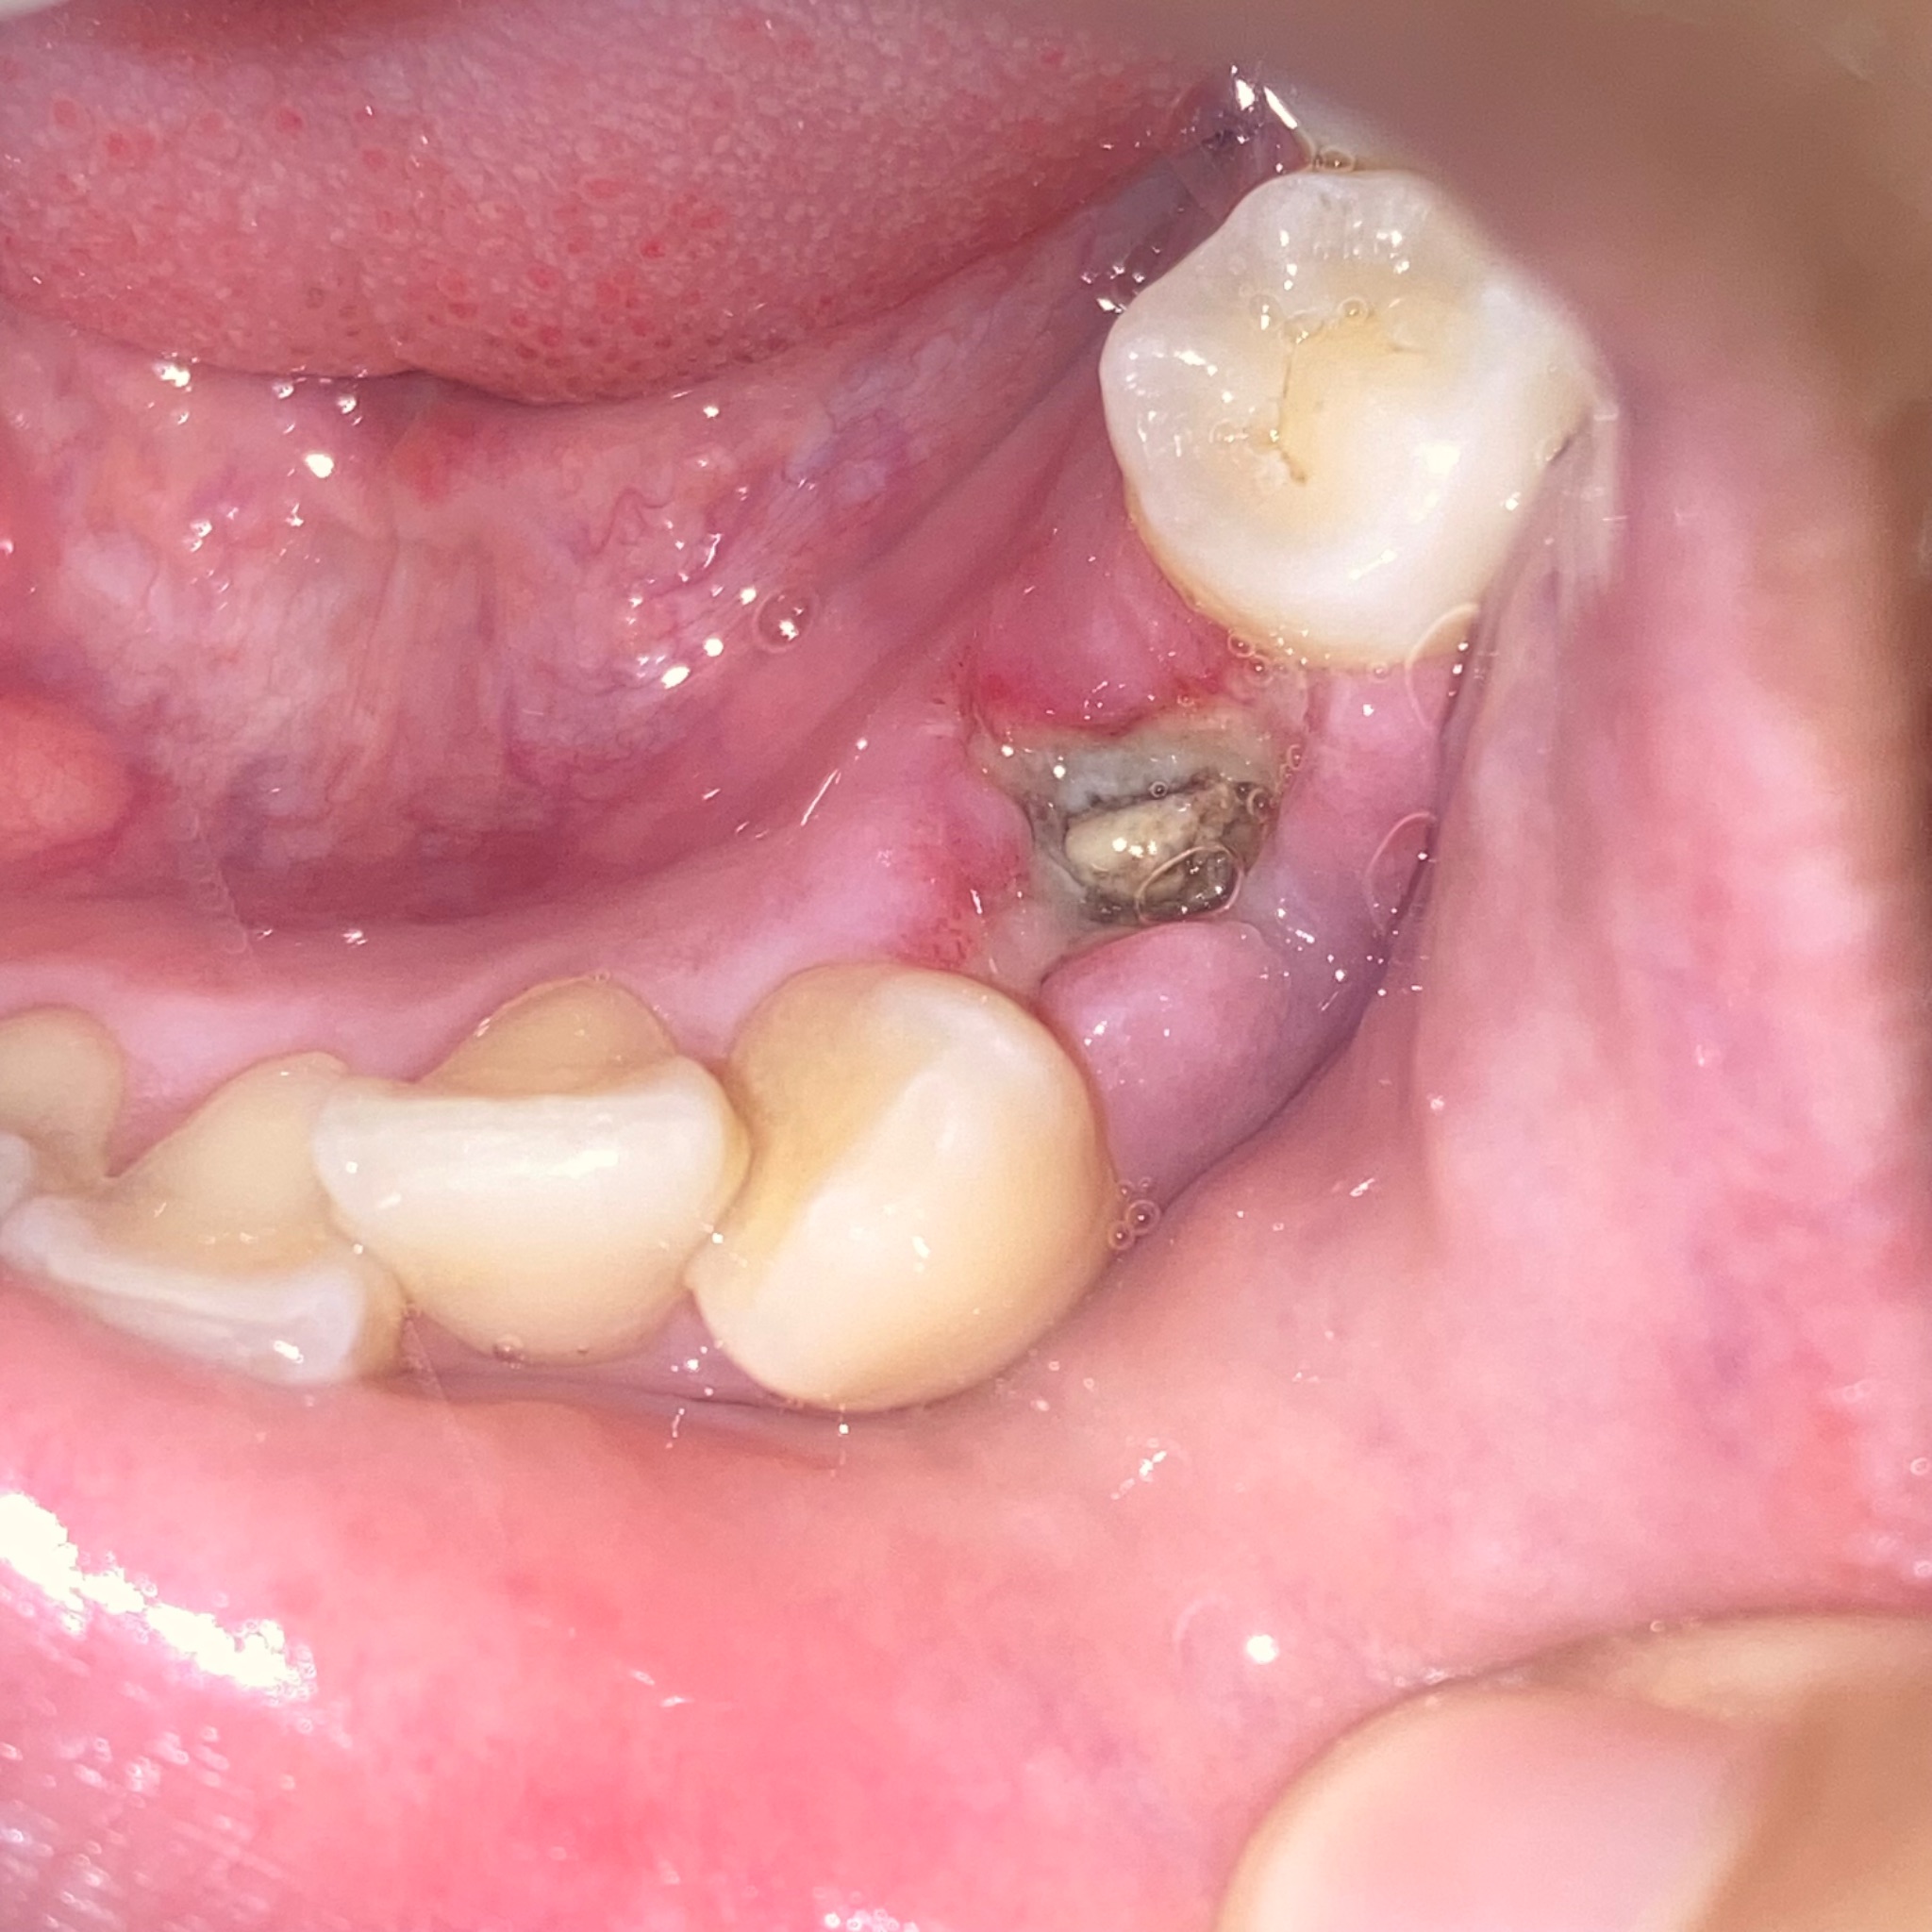

พอมาวันนี้ตุ่มบวมขึ้นมาก (รูป 3) เมื่อกี้มีเลือดไหลออกมา แบบนี้คืออาการอะไรหรอคะ

กังวลมากเลยค่ะ ต้องรอไปพบหมออีกวันจันทร์ เพราะเสาร์อาทิตย์ แผนกทันตกรรมปิด